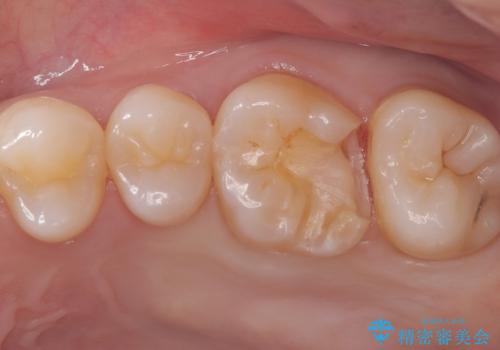

- 主訴:舌で触ったら歯に穴が空いていた。しみたりはしていない。

左上6番目の歯の噛む面に穴が空いていました。穴自体は小さいものでしたが、歯の中で虫歯が広がっていることが確認でき、虫歯の大きさを考慮しインレーでのやり替えとなりました。

咬合面に穴が空き、歯の中でう蝕が広がっていました。この歯が過去に咬合面う蝕を経験しCR修復を受けていること、今回歯質とCRの境目からの二次う蝕になっていることを説明し、適合や材料安定性の良いセラミックインレーでのやり替えとなりました。